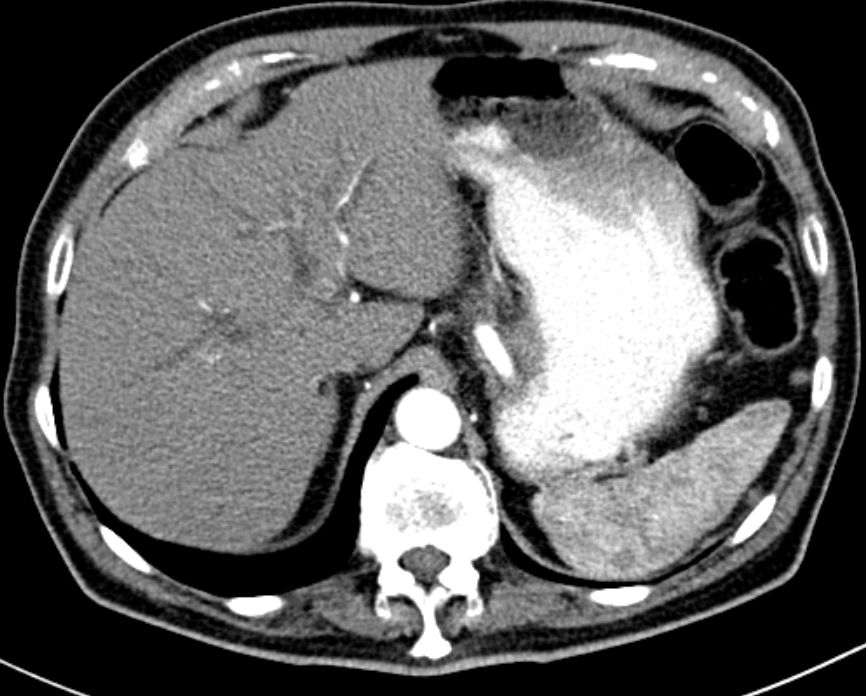

Das CT zeigt eine erweiterte Gallenblase mit

Stein. Prominenter Pankreaskopf. Nierenstau links.![]() | ||||||||||||